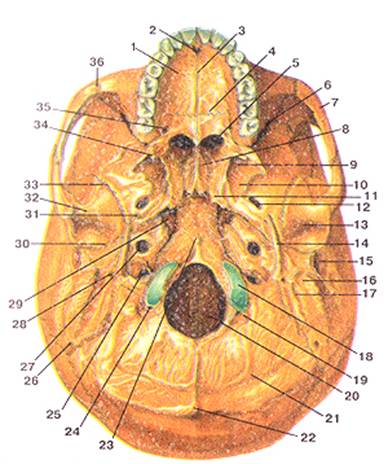

Анатомические детали: Фотографии топографии черепа с нижнего вида